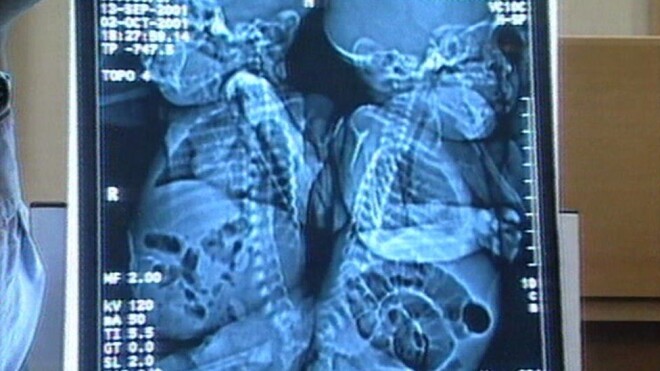

Māsas Emana un Sančia dzima priekšlaicīgi 2001. gada 13. septembrī ar daļēji savienotu mugurkaulu. Trīs mēnešus vēlāk Birmingemas bērnu slimnīcā viņām tika veikta veiksmīga atdalīšanas operācija. 16 stundu ilgā procedūra bija pirmā šāda veida operācija Lielbritānijā, bet trešā – pasaulē.